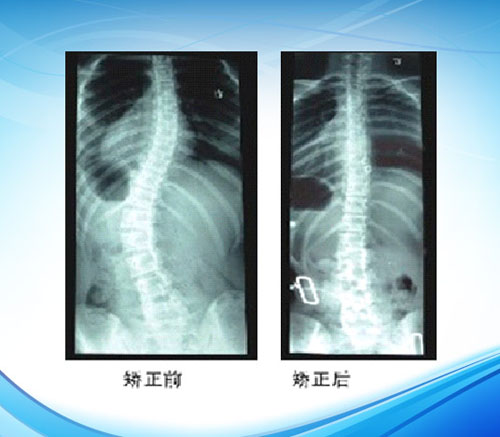

脊柱侧弯矫形器

使用说明:产品为定制产品,需按大小或形状进行修改和调整。通过额状面上三点压力,一定程度的腹部压力,最终改变胸廓脊柱的形状。

脊柱侧弯的矫形器治疗方法即通常所说的支具疗法,是矫正中度脊柱侧弯的有效方法之一。对于手术治疗适应证之外、需要非手术治疗的发育期儿童,装配一定形式的侧弯矫形器,同时采用侧弯体操疗法改善肌肉的矫正力量,采用牵引疗法改善脊柱的柔软性,能达到控制脊柱发育、防止畸形加重、矫正侧弯的目的。脊柱侧弯的矫形器疗法也是配合手术矫正、电刺激疗法的手段之一。